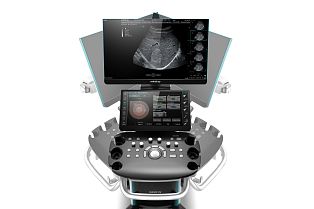

Philips Affiniti 50 ультразвуковой аппарат

Характеристики Philips Affiniti 50 ультразвуковой аппарат

- Сенсорный экран планшетного типа

Экспертный УЗИ сканер Philips Affiniti 50 для исследований любой сложности в любых областях включая акушерство и кардиологию. Система удовлетворяет ежедневную потребность в быстром сканировании и достоверности предоставляемых результатов, используя инновации, которые делают ультразвуковые системы компании Philips. Технологии, сокращающие время обследования для комфорта пациентов, и сохранения ресурсов врачей.

- Сенсорный экран планшетного типа